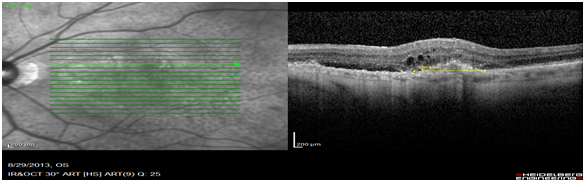

Images of patients (n=63) of patients who had classic type 2 CNV was retrospectively analysed. OCT images obtained on the Heidelberg spectral is at diagnosis were compared to the FFA images obtained on the same day. The OCT biomarker, the sub retinal hyper reflective mass (SRHRM) was used. The same photographer was used to minimise bias. The sub retinal hyper reflective mass was used as the OCT biomarker. The size of this SRHRM was measured at its widest using the caliper setting. This was then compared to the widest diameter of the CNV leakage measured on ultra high-resolution spectral is FFA by drawing a circle around the leage and noting its diameter (Figure 1A,1B & 2A,2B).

Figure 1A Measurement of SRHRM on the OCT scan using the caliper measurement (1353m).

Figure 2A Measurement of SRHRM on OCT scans using the caliper measurement (1654m).